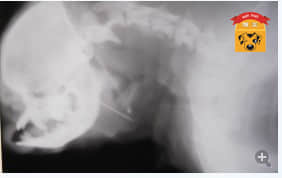

3月10日带来复诊,头颈部X光正侧位显示咽喉下方有一根缝衣针斜插到食道外。